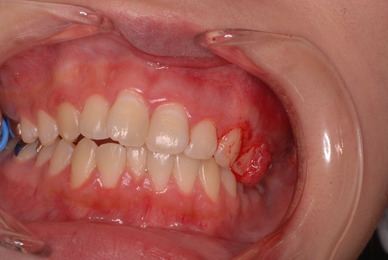

歯周病の疑いで東京のかなり遠方の方が来院されました。

驚くべきことですが、定期検診は受けていたそうです。しかしながら歯周病の指摘は受けたことがないそうです。

何故か?定期検診が虫歯のチェックのみになり、又肝心の歯周病の検査や歯周病の部分の予防や治療のためのブラシの使い方などを学んだ事がないのです。